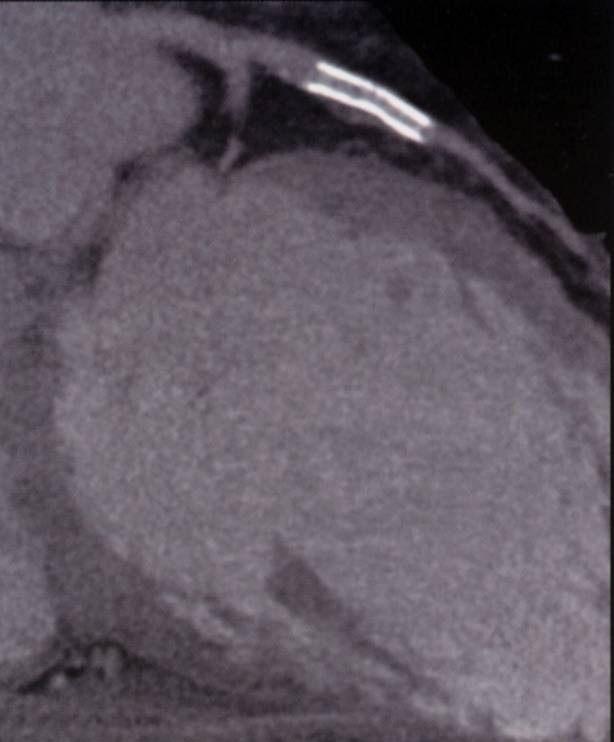

The non-invasive imaging modality of multi-detector computed tomography has dramatically evolved the last ten years and that is due to hardware and software developments. The newer generation of scanners allows increased spatial and temporal resolution that improves the clinical reliability giving further insights into the evaluation of coronary artery disease. Heart morphology imaging followed by studies of myocardial function and assessment of cardiac valves can be performed from the information derived from the data of the coronary artery examination. Also, the venous anatomy of the heart, coronary artery bypass grafts, stents, and cardiac tumors can be imaged and evaluated when necessary. For the beneficial use of this method, entrance criteria for different patient groups need to be set in order to allow improved outcome of multi-detector CT.